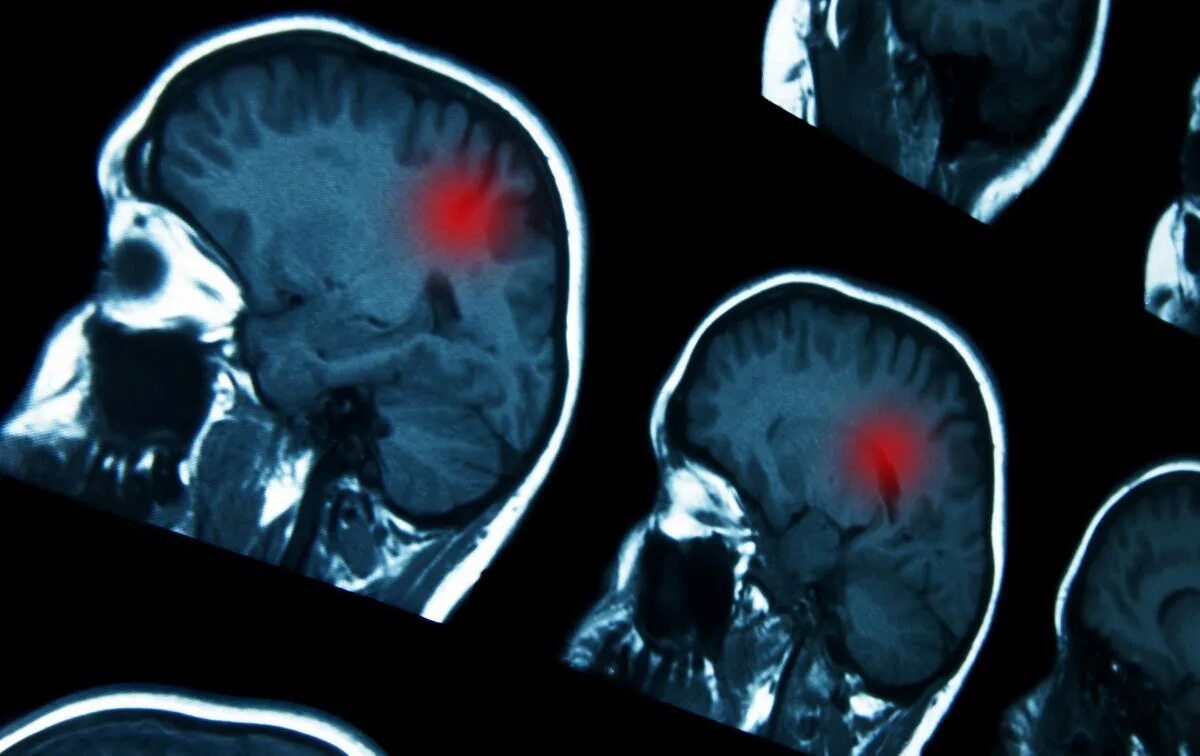

Как умирают от рака головного мозга